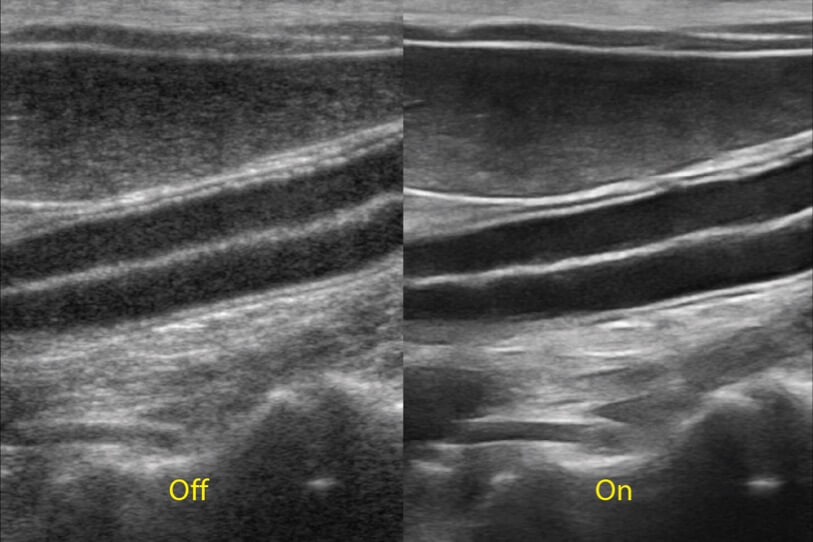

ProPet 70 進(jìn)一步提升了微米成像算法,更加注重對(duì)基礎(chǔ)原始圖像的還原和保留,在有效減少斑點(diǎn)噪聲、增強(qiáng)組織邊界顯示的同時(shí),避免過度優(yōu)化丟失真實(shí)的解剖信息。